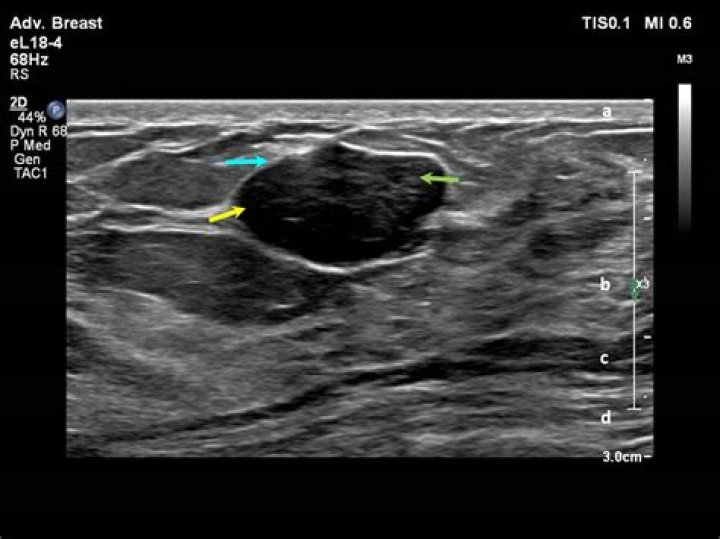

A hypoechoic mass is tissue in the body that’s more dense or solid than usual. This term is used to describe what is seen on an ultrasound scan. Ultrasound uses sound waves that are absorbed by or bounce off of tissues, organs, and muscles.

Solid masses are hypoechoic and can be cancerous. Cysts filled with air or fluid are usually hyperechoic and are rarely cancerous. Abnormal tissue also looks different from healthy tissue on a sonogram. Your doctor will usually do further testing if an ultrasound shows a solid mass or what looks like abnormal tissue.

As defined in the US lexicon (1), circumscribed margins are well defined or sharp, with an abrupt transition between the lesion and the surrounding tissue. Noncircumscribed margins encompass the remaining margin descriptors, including microlobulated, indistinct, angular, and spiculated.

On ultrasound, a breast cancer tumor is often seen as hypoechoic. It has irregular borders, and may appear spiculated. Other ultrasound findings that suggest breast cancer include: Nonparallel orientation (not parallel to the skin)

Ultrasound. On ultrasound, fibroadenomas typically appear as oval, parallel, circumscribed, uniformly hypoechoic masses with echogenic, thin fibrous internal septations (Figure 1B, 2A) and variable posterior features.